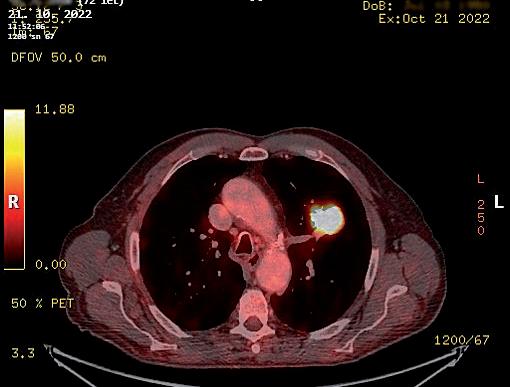

obr. 3.4 Adenokarcinom plicní po neoadjuvanci indikovaný k operačnímu řešení u 65letého muže na CT (a) a PET CT (b) obraze je masou nádoru natolik objemný (v největším rozměru prakticky 10 cm), že postihuje více než objem jednoho segmentu horního laloku levé plíce. Pro bezpečné vyjmutí resekátu nádoru, laloku plicního, je v tomto případě nutná regulérní torakotomie. Nádor dosahuje blízkosti odstupu tepenných větví pro horní lalok. Takový nález není vhodný pro videoskopické řešení. Výkon z torakotomie v takových případech upřednostníme. Po otevřené horní lobektomii vlevo a kompletní spádové lymfadenektomii nebylo patologem u pacienta nalezeno žádné nádorové postižení uzlin

Pro posouzení indikace k operaci je ideálním stavem ná dor již histologicky verifikovaný jako maligní nemalobu něčný tumor plic a aktuální PET CT vyšetření zobrazující úroveň metabolické aktivity ve spádových lymfatických

uzlinách. Indikující chirurg je však často v situaci, kdy se primární ložisko v plíci podezřelé z maligního původu nezdařilo verifikovat bronchoskopií s biopsií nebo kar táčkovou cytologií, ani punkční transparietální biopsií pod CT (obr. 3.9, 3.10).

Na tomto místě je potřeba z praxe uvést, že výraz nou pomocí pro předoperační posouzení, jestli je nádor plíce zhoubný nebo nezhoubný, nemusí být ani PET CT [35, 36], které je v dnešní době jinak zásadním vyšet řením (obr. 3.11). Nevelké metabolicky aktivní ložisko i s aktivitou spádových uzlin může být počínající plicní malignitou, ale také zánětlivým procesem (obr. 3.12). Objemnější, asymptomatický, náhodně objevený, cent rálně v laloku umístěný nádor s výraznou metabolickou aktivitou, včetně nepravidelné metabolické aktivity uz lin u uhlokopa, může být jen koniotickým uzlem (obr. 3.13). Naopak jako neaktivní nemusí být zobrazeny pouze zhoubné nádory pod aktuálním kritickým roz lišovacím objemem pro PET CT (průměr léze 8 mm).